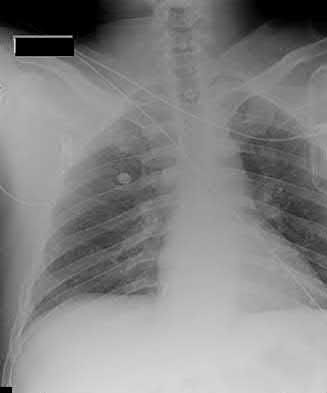

2. # A 35-year-old woman is involved in a head-on collision while driving. Initial radiographs are shown in Figures 8a and 8b. Injury to what vessel increases the risk for osteonecrosis of the injured bone?

5. Artery of the tarsal sinus Corrent answer: 4

The patient has a Hawkins type III talar neck fracture-dislocation with a risk of osteonecrosis ranging from 69% to 100%. Anatomic studies have shown that the artery of the tarsal canal supplies the lateral two thirds of the talar body.

The other vessels listed provide no significant contribution to the talus.